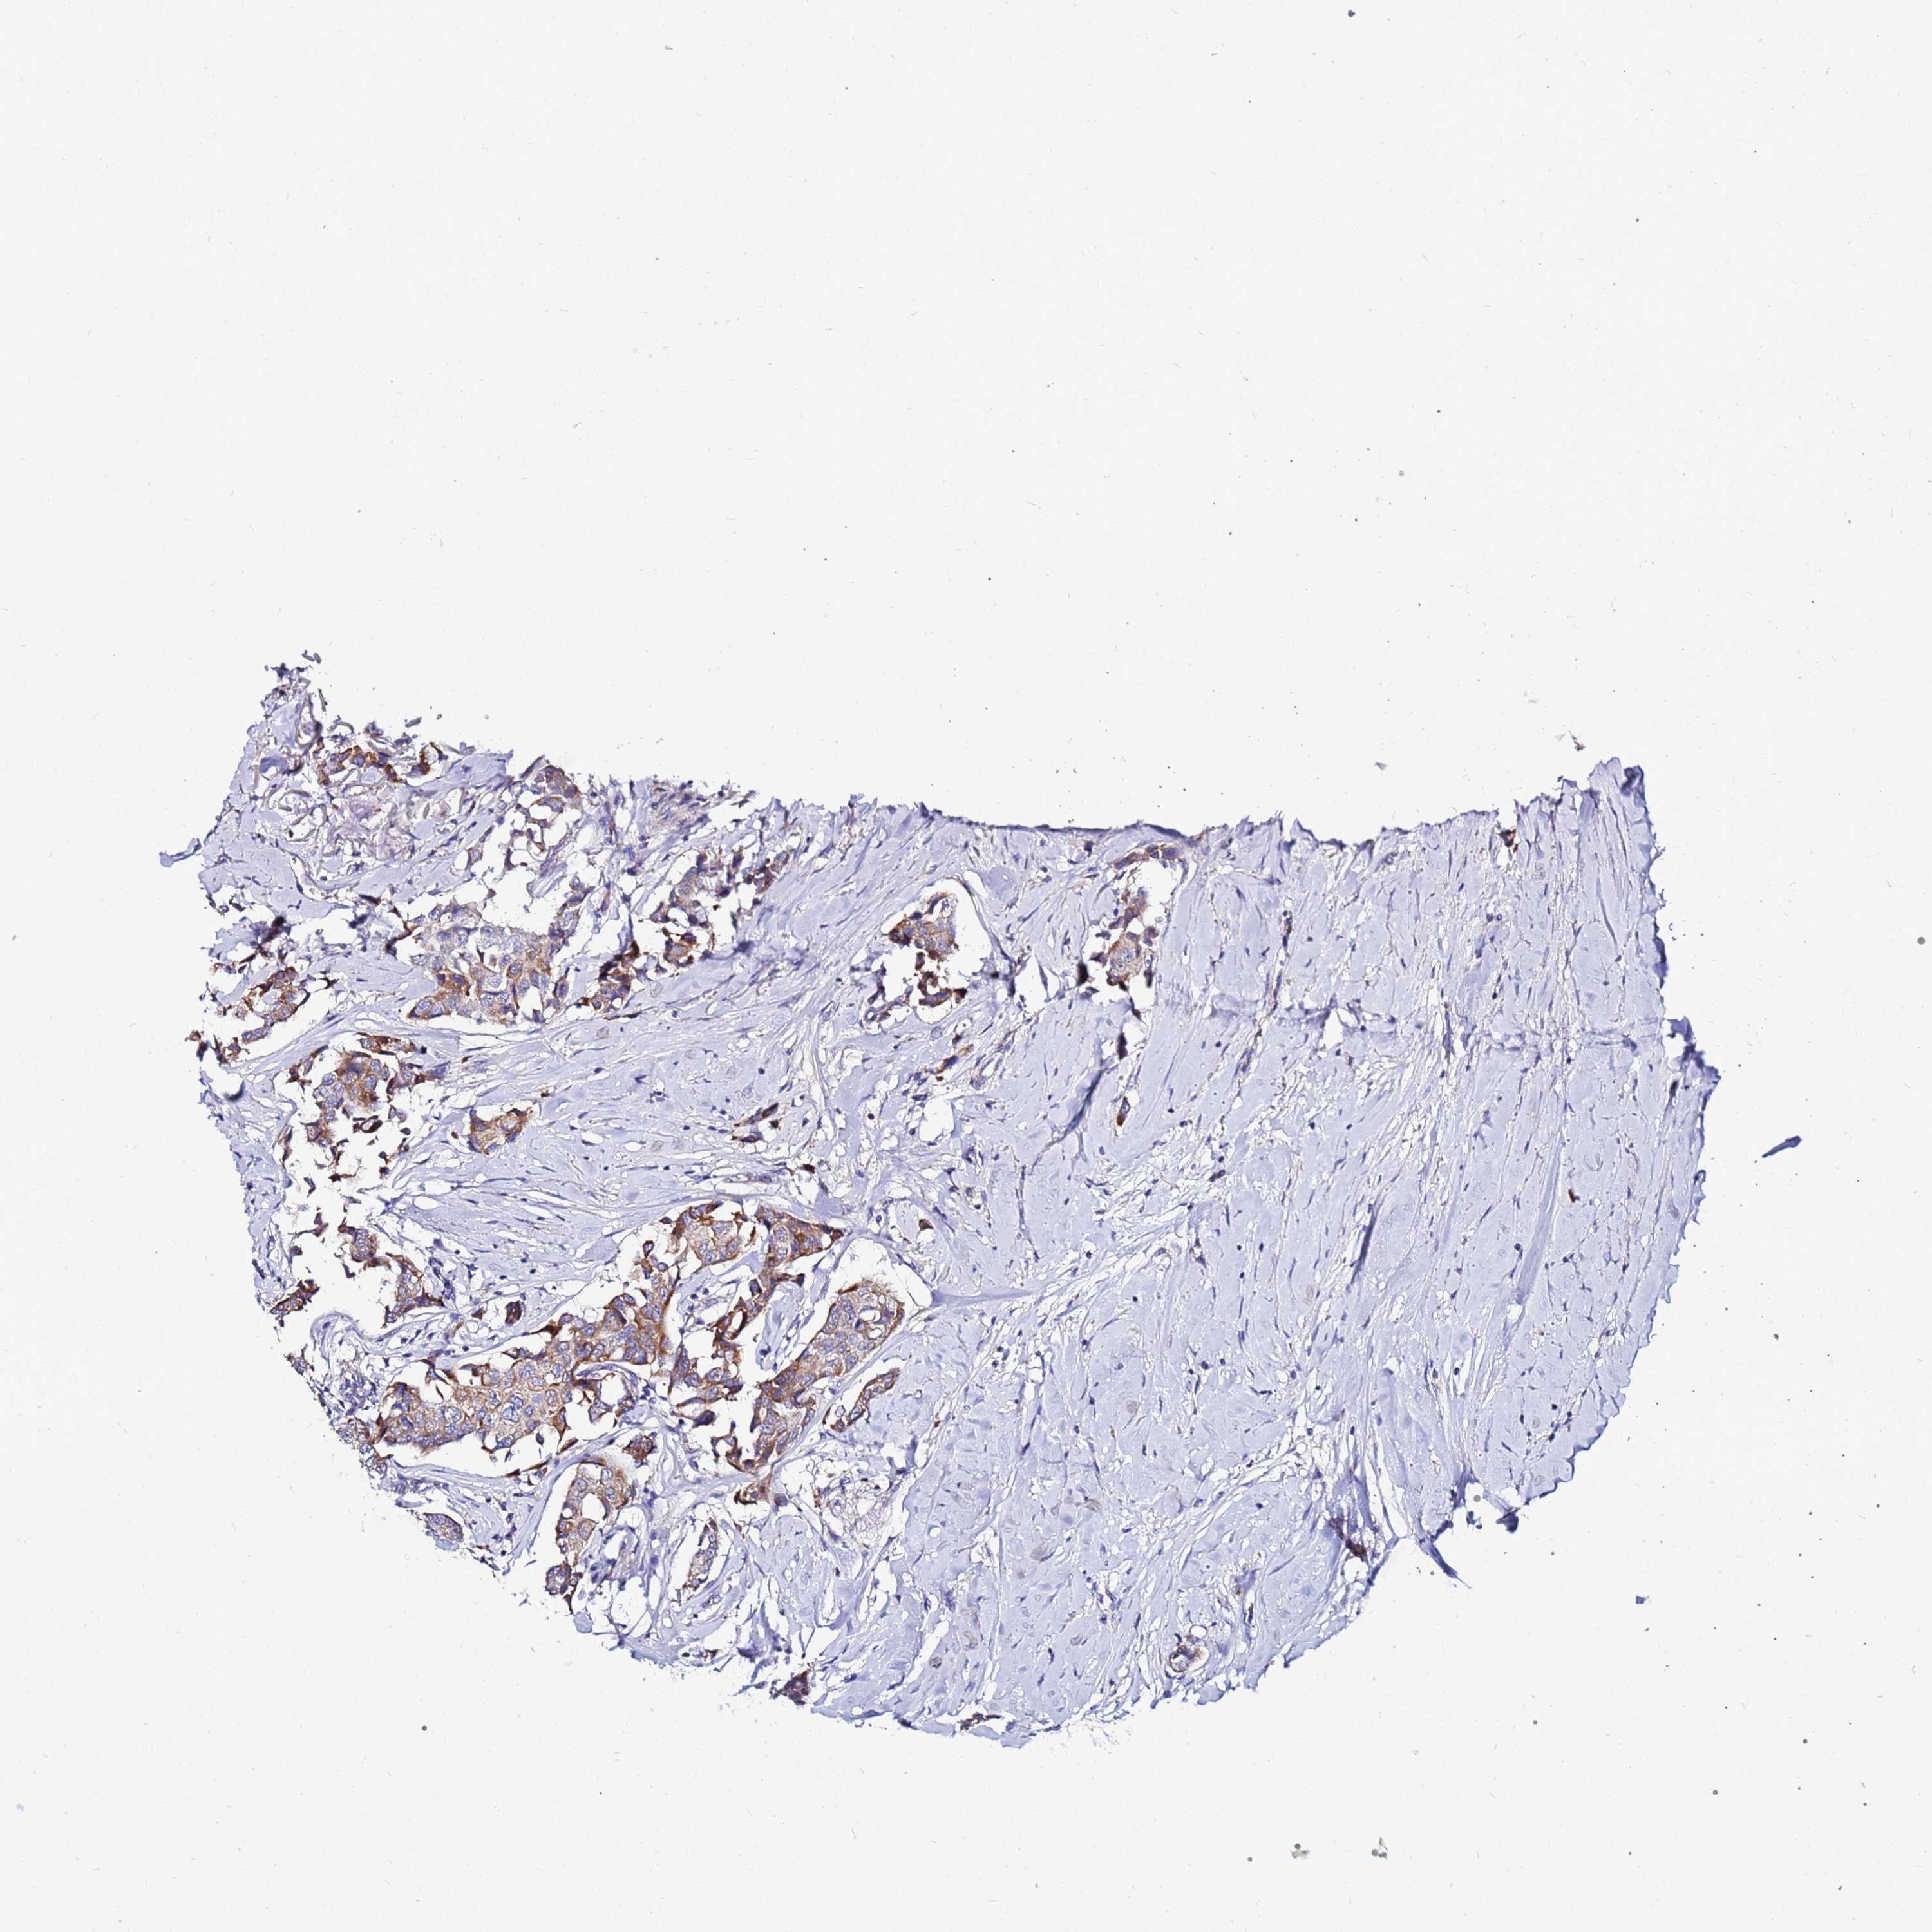

CANCER BREAST CANCER Show tissue menu

BRCA TCGA BRCA VALIDATION PROTEIN EXPRESSION